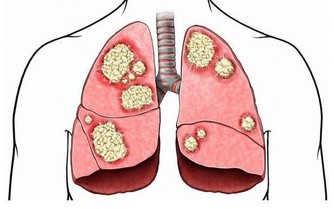

徵兆五:腎臟問題

腎功能不全,會引起腎的病變。腎的病變會讓糖尿病患者腎臟出現一定的不良反應。